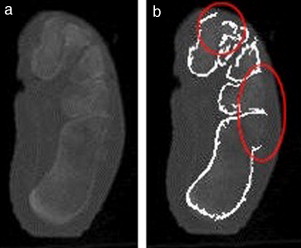

La figura 12 muestra los errores de la segmentación en un corte del pie de adulto 3. Se observa (fig. 12 b) que los contornos que representan el calcáneo y el cuboides no se definen correctamente y aparecen fusionados. De igual forma, no se obtiene una correcta definición de las 3 cuñas (fig. 12 b).

Ejemplo de fallo de la segmentación en una imagen de TC de baja resolución ...

Figura 12.

Ejemplo de fallo de la segmentación en una imagen de TC de baja resolución espacial. a) Imagen original; b) imagen con los contornos determinados.

Esta ambigüedad en la definición de los contornos de los huesos generalmente ocurre a causa de la baja resolución espacial de las imágenes, lo cual dificulta, incluso para un experto, la segmentación de tales imágenes.